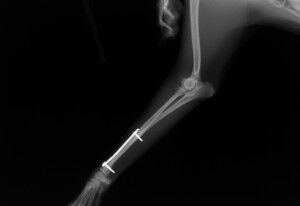

その後、1か月普通に生活していました。レントゲンを撮ったところ、骨は十分に増生していたので、心配ないと判断しプレートを取りました。プレート除去前

プレート除去後

プレート除去後は何の問題もなく生活しています。うまくいきました。